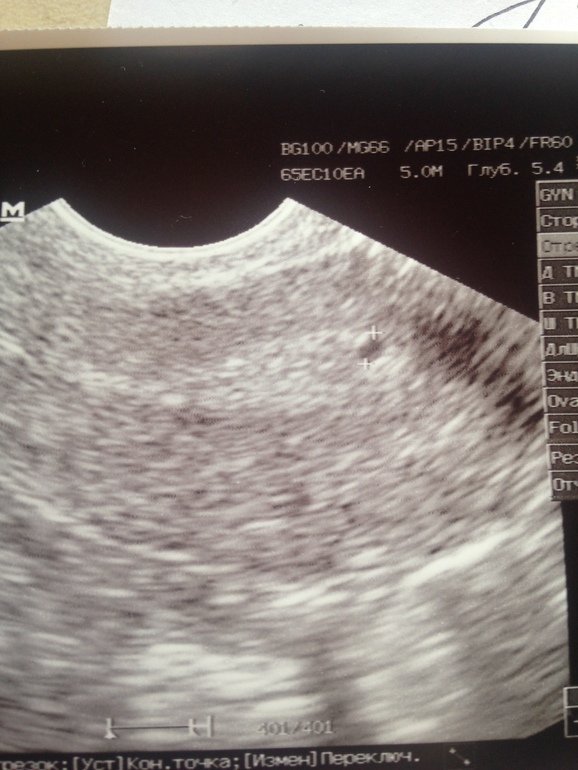

Добрый день,девочки.Дано:35ДЦ,задержка уже ну как минимум 3-5 дней...Тесты отрицательные ,на 23 ДЦ нашли в эндике включение 0,34 мм.Овуляцию чувствовала на 15-17 дц (точно не помню но не раньше ,не позже)резкая боль в ЛЯ,чуть розово-красных выд-ий.Сегодня УЗИ :Эндик 7мм(однородный)в ПЯ ЖТ 13мм??На 90%ЖТ как сказал врач.А мне вот не кажется,что это похоже на ЖТ,но я не врач,хз.В ЛЯ только фоллики..И никакого образования в Эндик нету(специально не сказала ,что там что-то находили,для чистоты эксперимента)Но когда будут М не сказали,ЖТ или нет не понятно.Да и чувствовала я 💯 процентов слева!!!Прилагаю фото,где два снимка -это сегодня ПЯ и ЛЯ,где один с точкой это включение -на 23 дц,ну и последний сегодня эндик .Как думаете,ЖТ???

А мне от этого,что я и не жду беременность,потому что мы предохраняемся))Хоть и ППА,но все же осечек небыло ...А вот циклы мне по 50 дней точно не нужны.Да и причём тут Б?Вопрос мой в том,похоже это на ЖТ или это фоллик!Т.к.врач сам не дал 100% ,что это Жт.Если ЖТ,то буду ждать М,а если нет,то дюфастон мне в помощь!